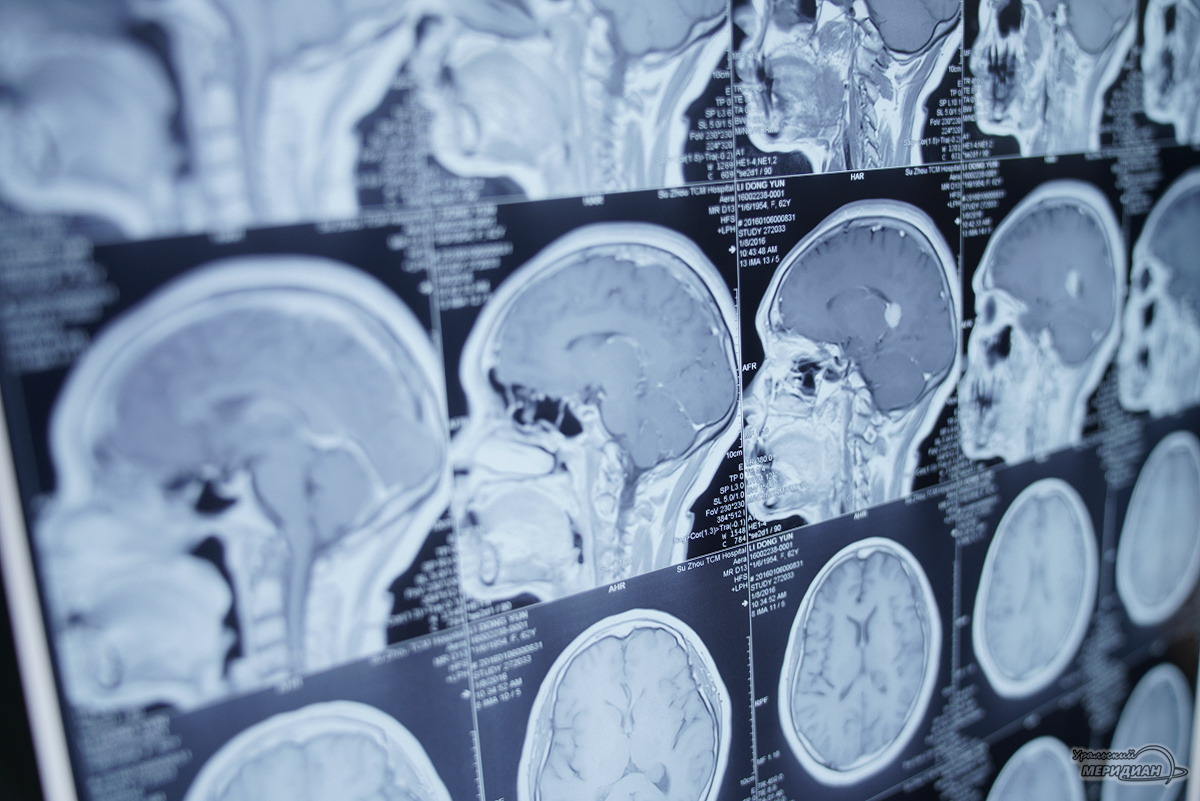

В Свердловском госпитале для ветеранов войн успешно проведена сложнейшая операция по реконструкции лица бойцу, получившему тяжелые осколочные ранения. Как сообщили в региональном Минздраве, военный поступил с множественными переломами глазницы и верхней челюсти.

Также у него была выраженная деформация лица из-за крупного рубца под глазом, что создавало угрозу потери зрения. Для подготовки к операции медики использовали современные технологии: с помощью компьютерной томографии создали 3D-модель черепа пациента, а затем изготовили индивидуальные биосовместимые импланты. В ближайшее время пациента ждет заключительный этап лечения — пластическая коррекция рубцовой ткани.

«Благодаря точным расчетам мы смогли восстановить анатомические структуры с точностью до миллиметра, что минимизировало риски и позволило добиться естественного результата», — пояснила заведующая отделением челюстно-лицевой хирургии госпиталя Анна Сусоева.